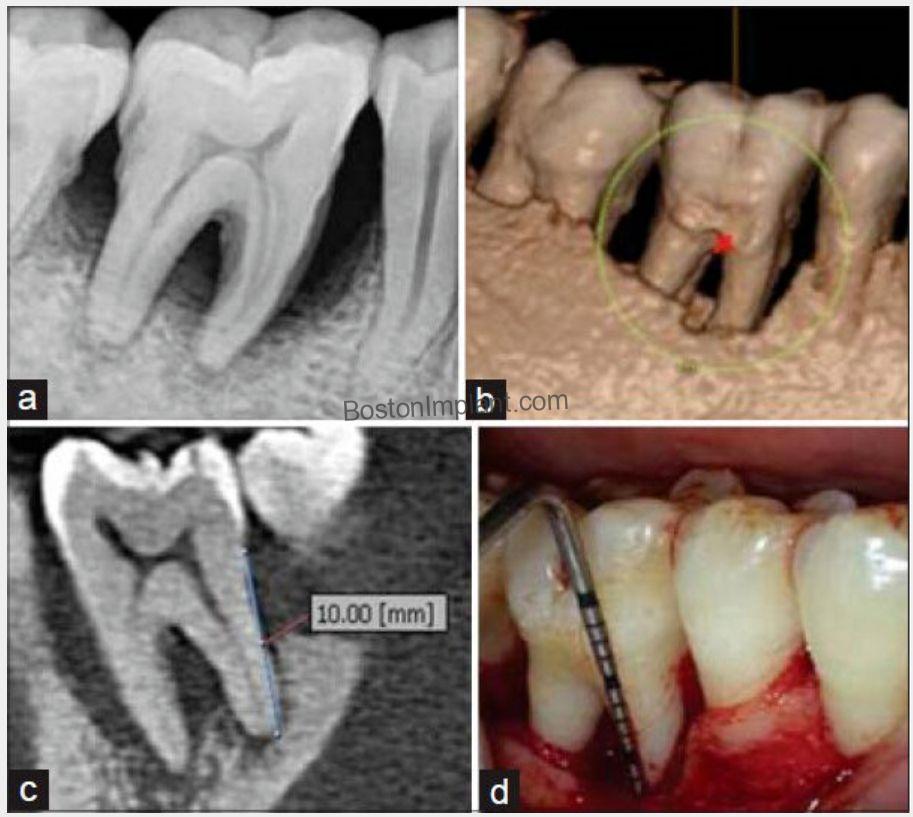

3. Periodontics (Gum Disease): Periodontitis, also known as gum disease, is a chronic inflammatory condition that damages the gums and bone supporting the teeth. Traditionally, diagnosis relied on tactile sensation, which could be uncomfortable for patients and wasn’t always accurate.

Thanks to CBCT, we can now diagnose gum disease easily and accurately.

5. Wisdom Teeth Assessment: Many wisdom teeth are impacted, and it’s often difficult to predict their exact shape and their relationship to the inferior alveolar nerve using traditional x-rays. Three-dimensional CBCT imaging provides the surgeon with the precise relationship, leading to more accurate diagnoses and safer treatment.